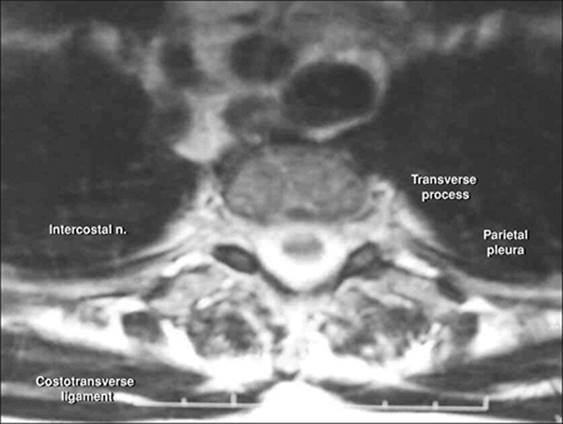

Anatomic Landmarks: Construct a vertical line joining the spinous processes of the thoracic vertebra corresponding to the nerves to be blocked. Palpate the edge of the sacrospinalis muscle and mark the lateral edge. The muscle will become broader as it extends caudad. A line is drawn along the edge of the muscle. The inferior border of the rib is marked and extended to bisect the line marking the lateral border of the muscle. The distance from the inferior border of the rib to the pleura is about 5 mm (Fig. 20-1).

Figure 20-1. Anatomic landmarks.